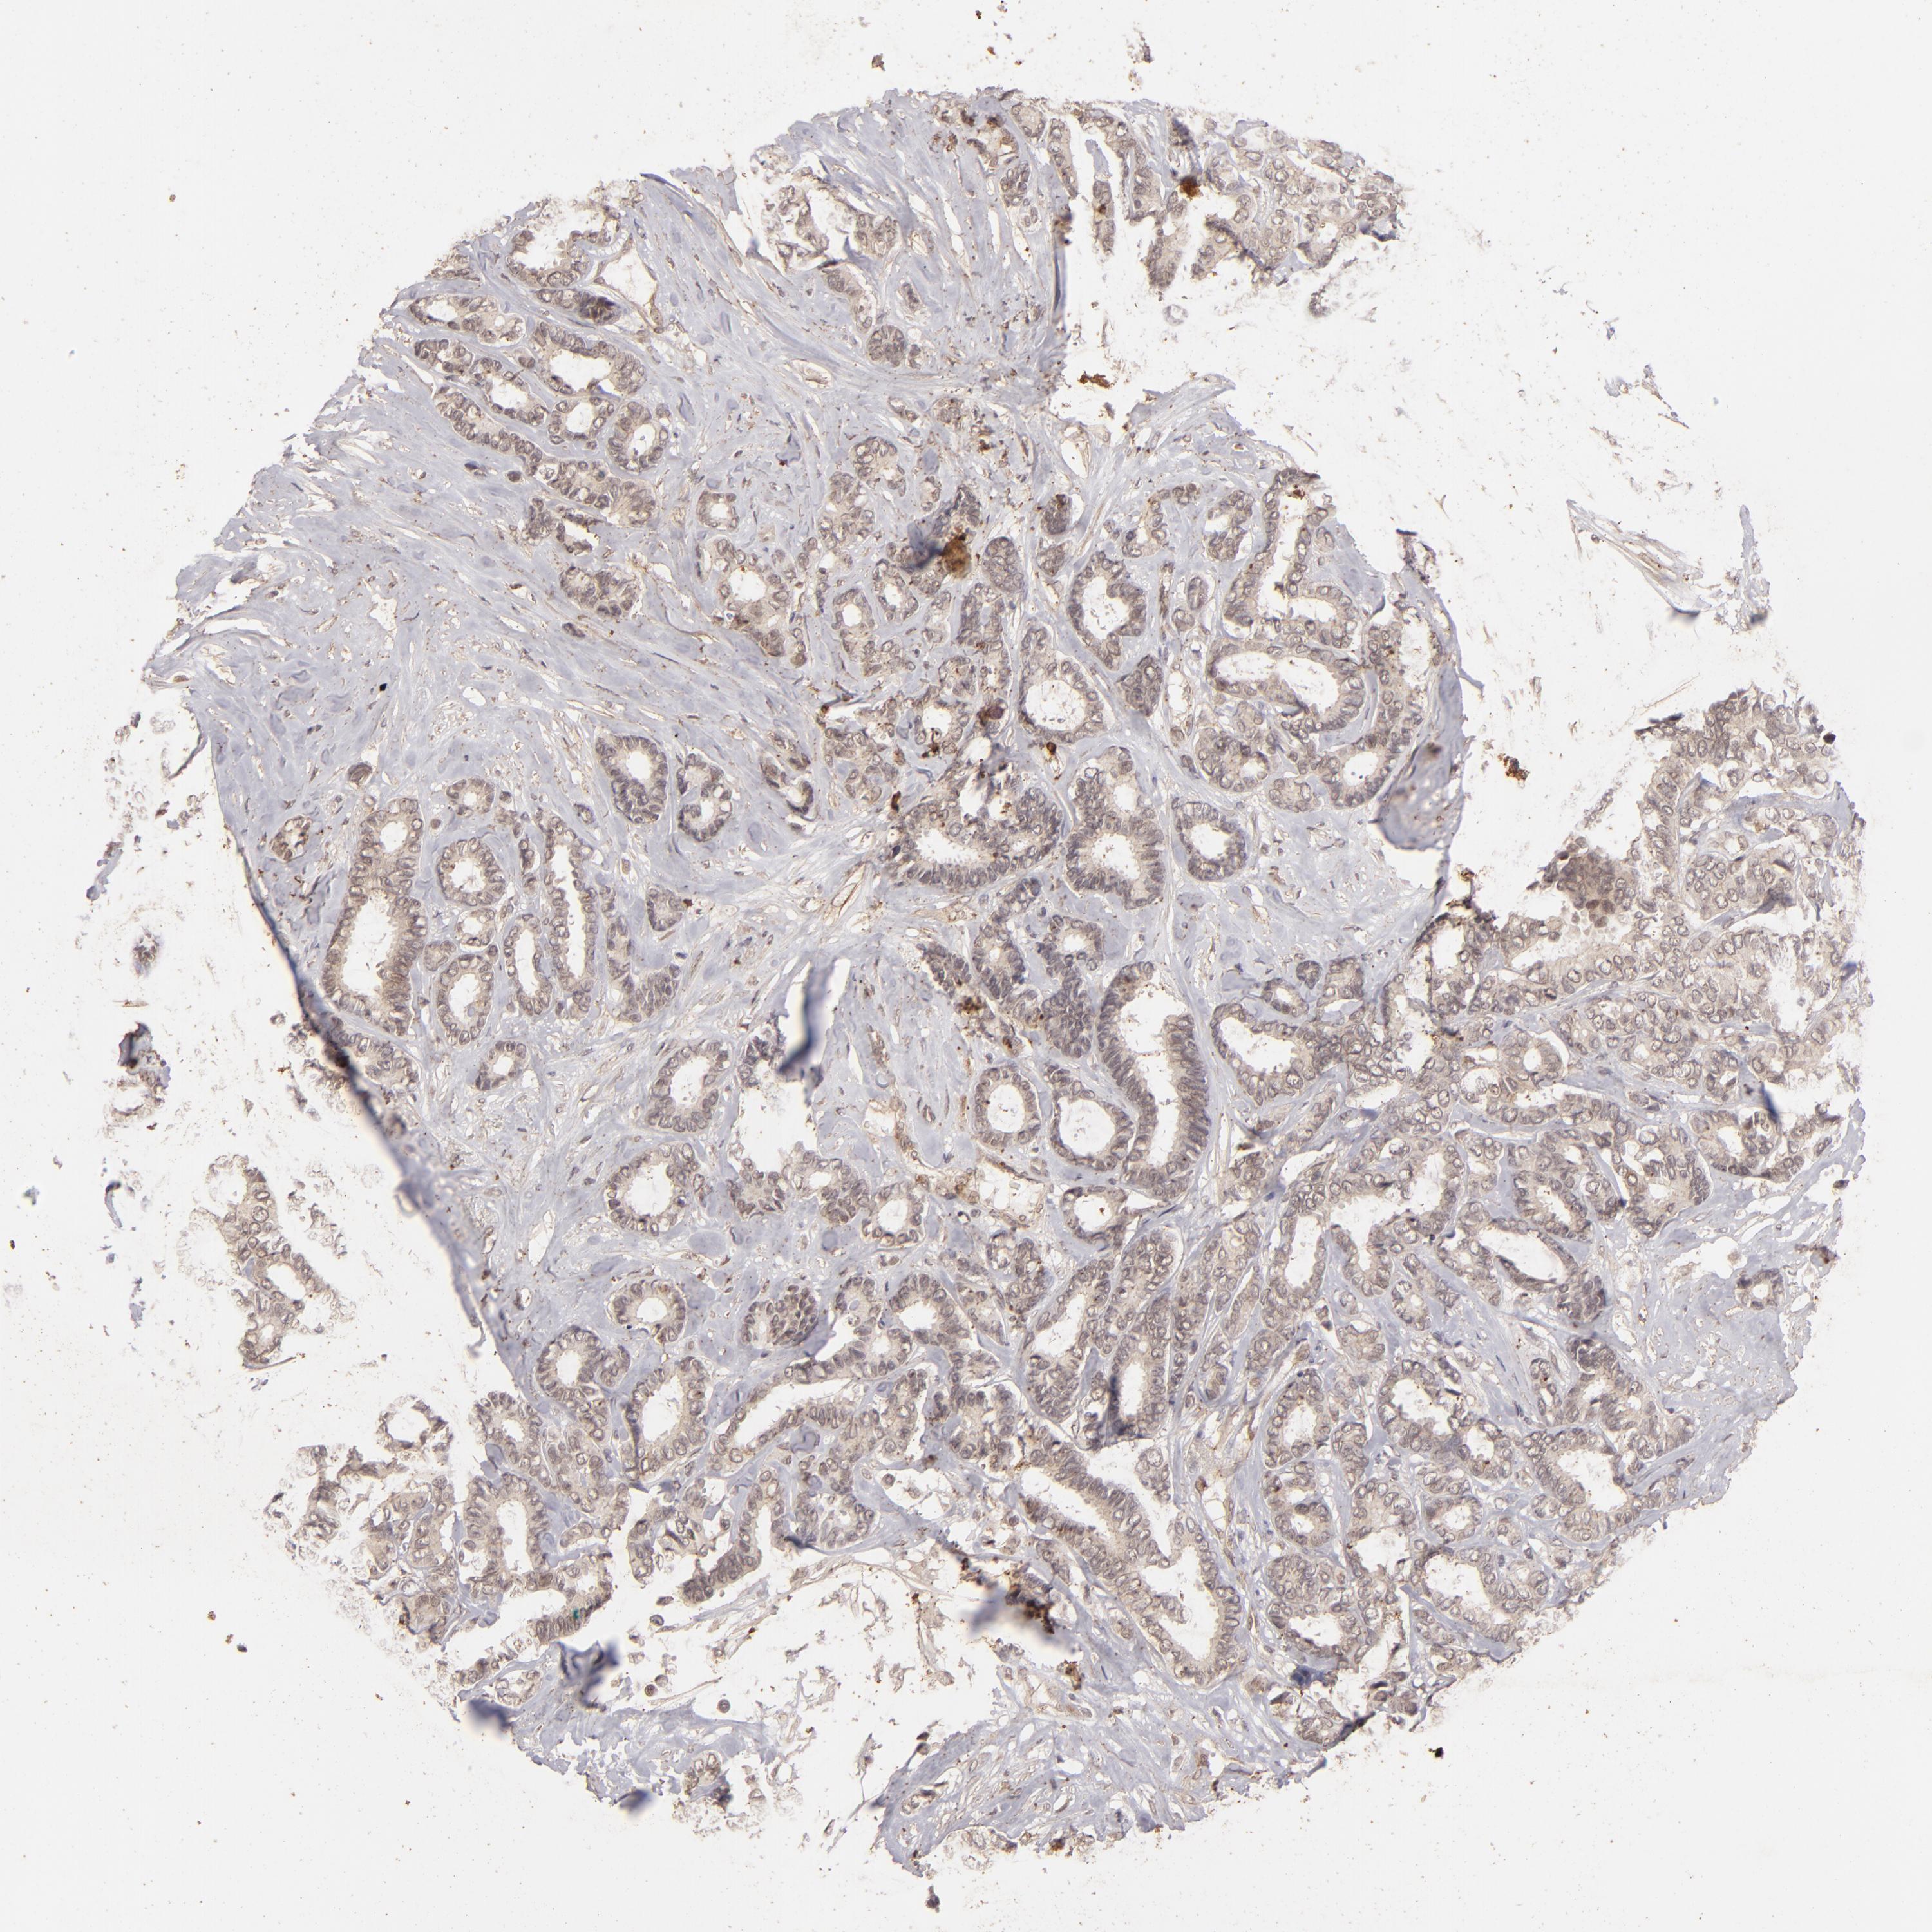

CANCER BREAST CANCER Show tissue menu

BRCA TCGA BRCA VALIDATION PROTEIN EXPRESSION